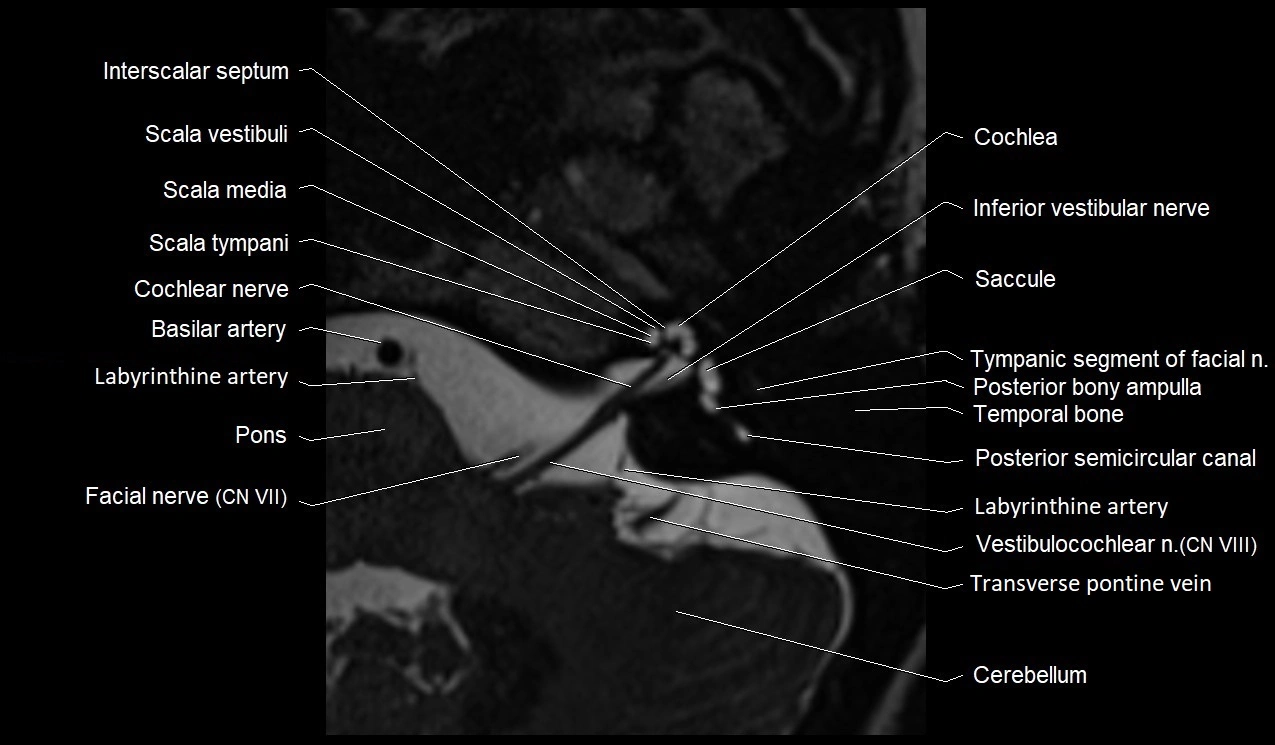

MRI Appearance

• The abducens nerve is a small, thin, linear structure

• Best visualized on high-resolution T2-weighted 3D MRI sequences (e.g., FIESTA or CISS)

• Seen as a hypointense (dark) line running from the brainstem at the pontomedullary junction, traversing the prepontine cistern, and entering Dorello’s canal under the petrosphenoidal ligament, then into the cavernous sinus, and finally the orbit

• May be challenging to visualize in standard MRI due to its small size

• Pathology may be inferred by absence, displacement, or enhancement of the nerve

MRI images

image